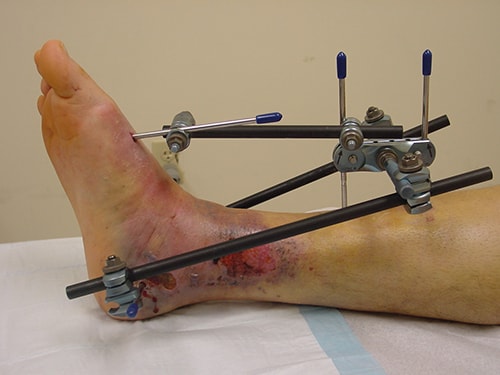

External fixation of a pilon fracture

An external fixator may be applied to protect your foot until it is safe to perform a second surgery to repair the fracture.

In this operation, your doctor makes small incisions into the skin and inserts metal pins through the bones. The pins project out of the skin and are attached to bars outside of the skin. The external fixator acts as a frame to help hold your ankle in a good position until a second surgery can be performed. The external fixator also helps to restore proper limb length and provides stability.